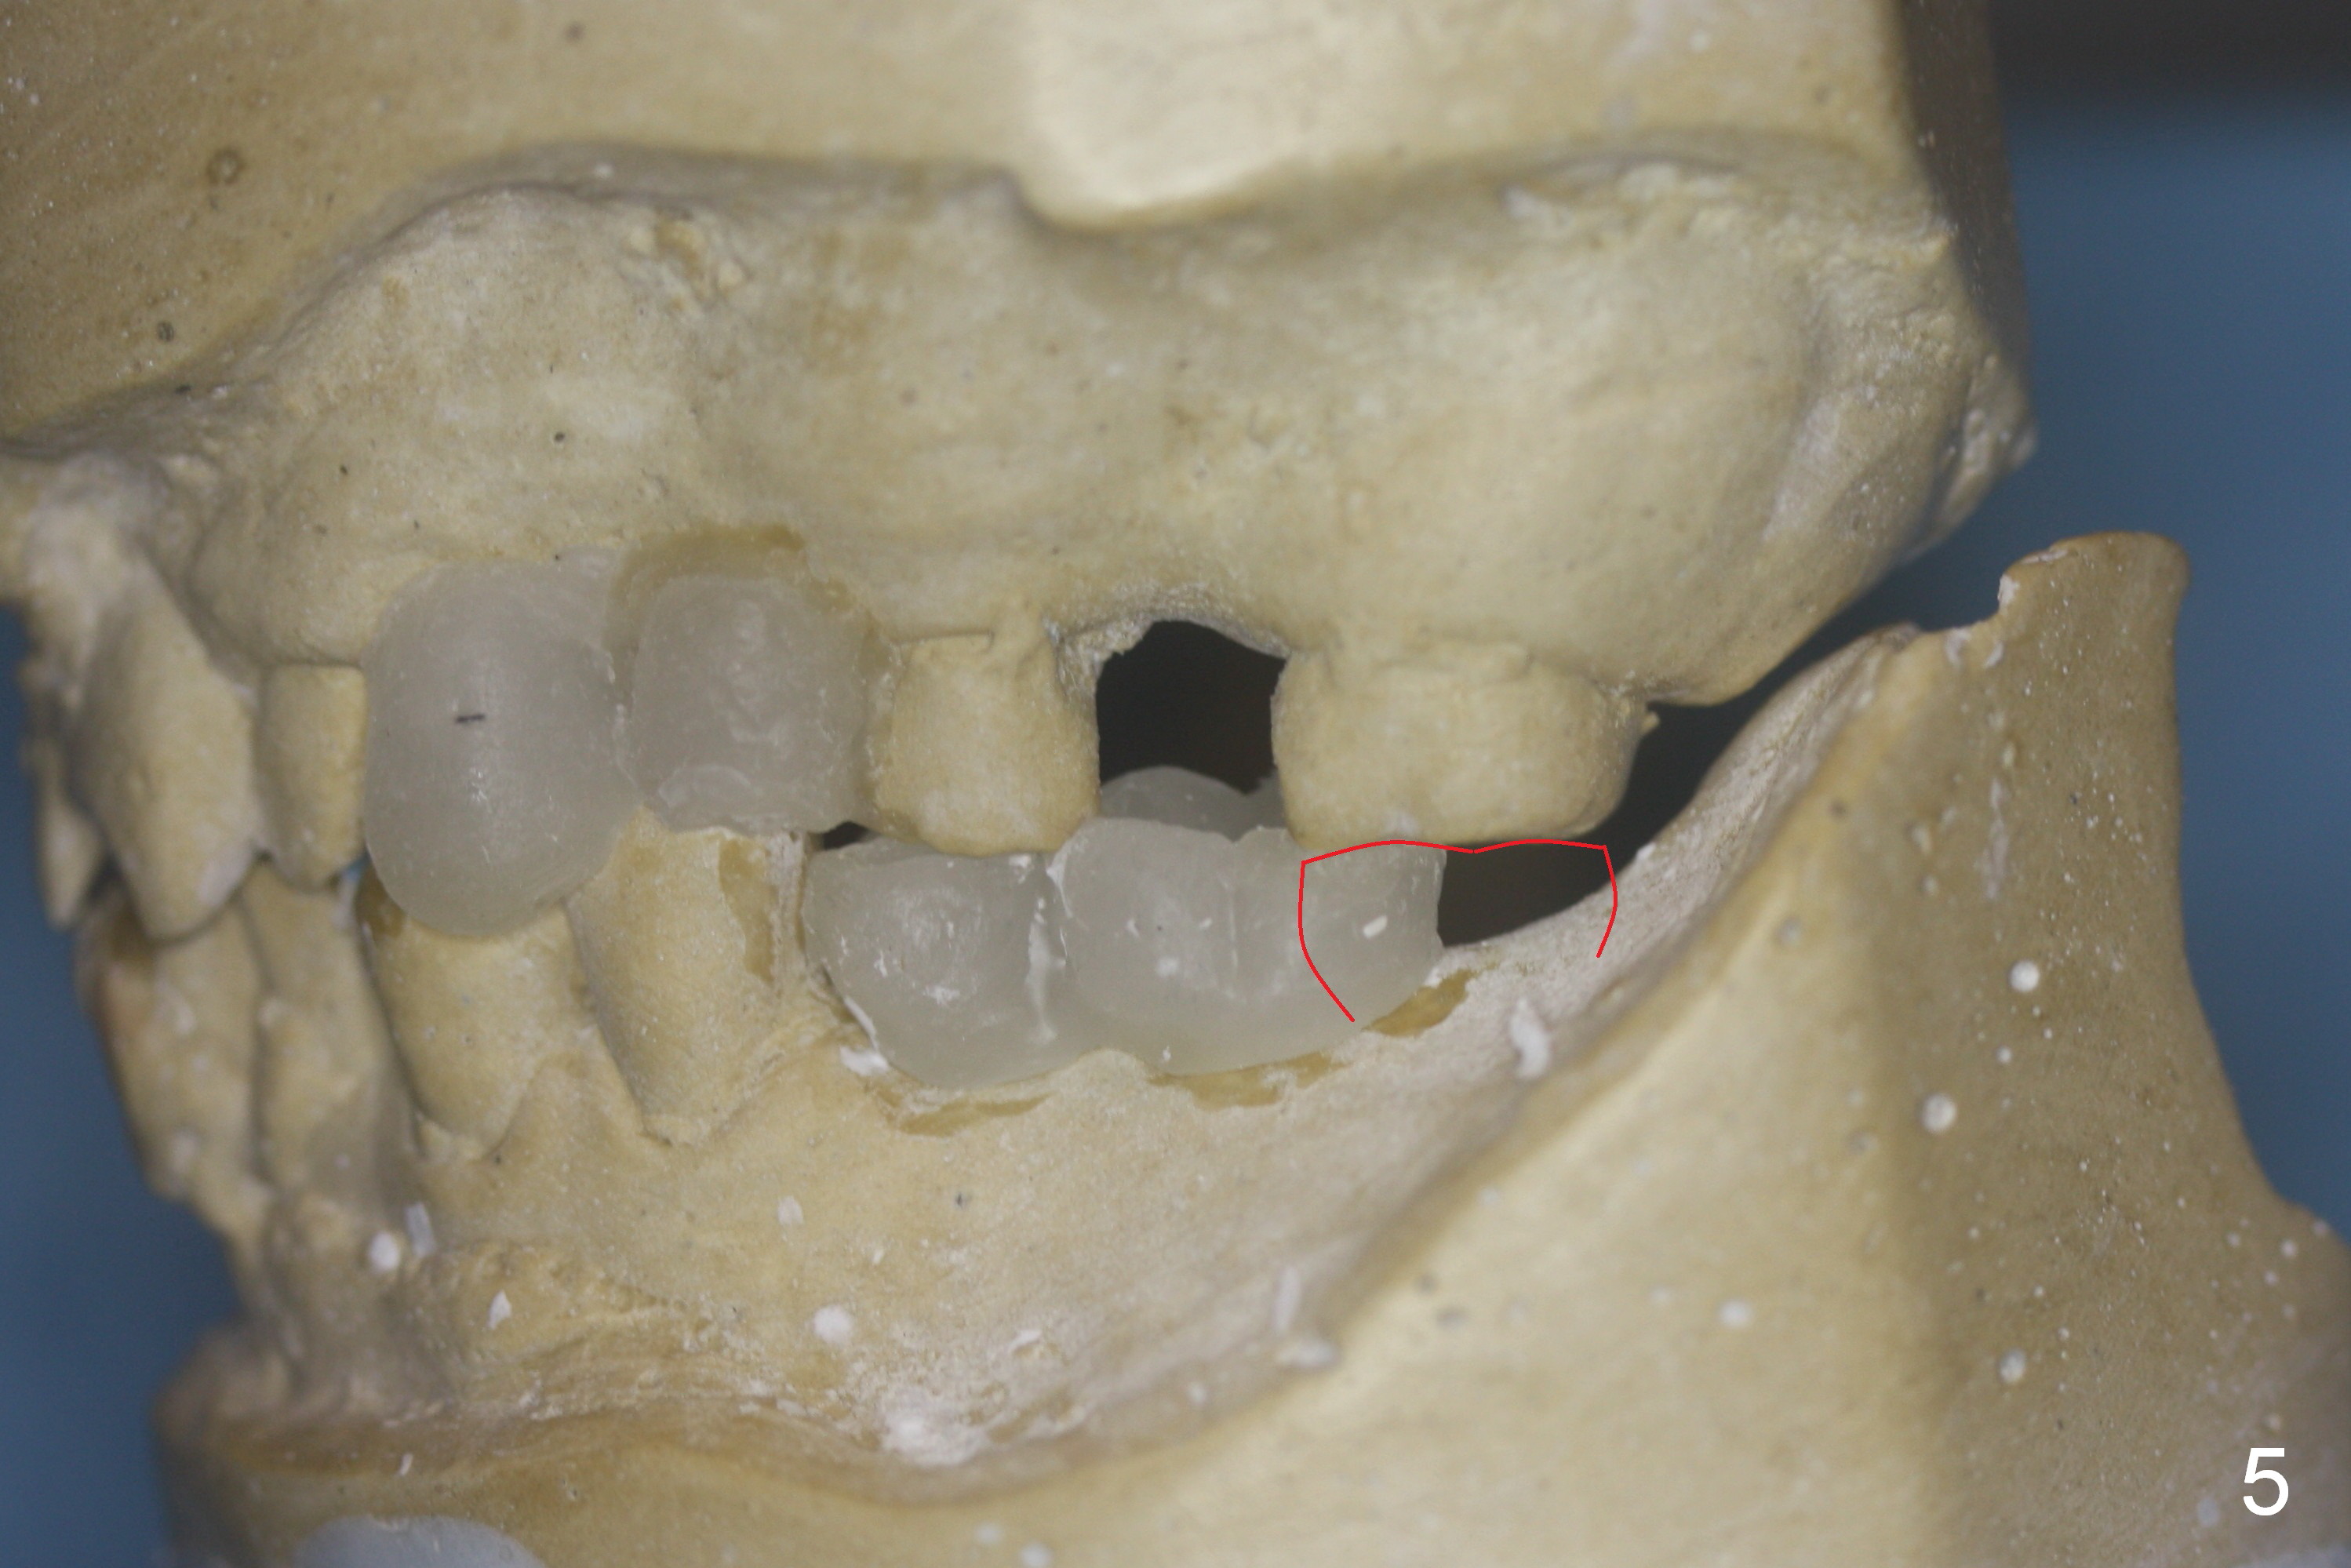

Restudy of the diagnostic wax up (Fig.4) reveals that the edentulous space at #14 is narrow mesiodistally. The pontic at #19 should be correspondingly narrow. Therefore the crown at #18 should be large (Fig.5 red outline). The initial entry point for #18 implant (Fig.6 (occlusal view of a surgical stent) *) should be immediately distal to #19.